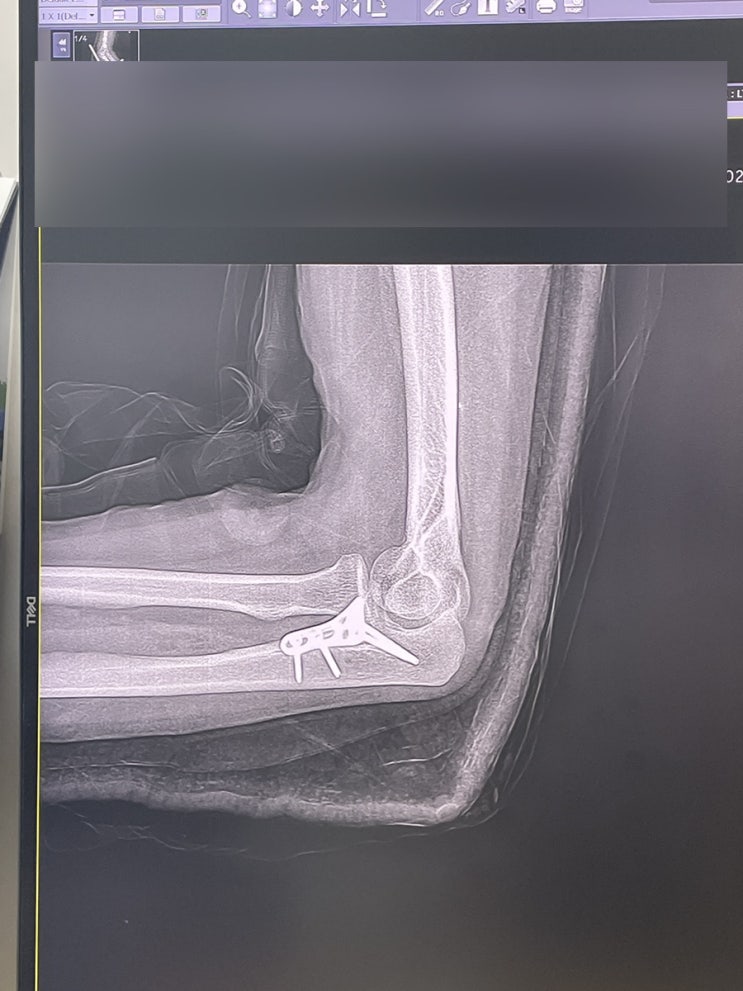

[골절일기] #2. 수술 전/후 입원, 반깁스, 보조기, 보험금 :: 팔꿈치 골절

"어쩌다 골절" 1편은 입원했을 때 가볍게 써봤는데 시간이 갈수록 더해지는 통증과 오랜시간 재...

[골절일기] #1. 보드타다가 팔 골절된 이야기 >_@ :: 팔꿈치 골절

팔 골절된지 일주일만에 쓰는 글 한 손으로 작성중^^ 병원에 입원하면 심심하고 할거 없을줄 알았는데 3끼 ...